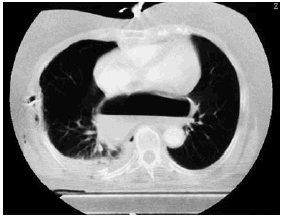

Mujer de 72 años sin antecedentes de interés, que ingresó en la Unidad de Cuidados Intensivos tras politraumatismo secundario a atropello. En los estudios radiológicos simples se objetivó fracturas de ambos fémures y de cúbito derecho, así como fracturas costales derechas junto con neumotórax y contusión pulmonar ipsilateral. Llamó la atención en la radiografía simple de tórax la presencia de una burbuja de aire a nivel centromediastínico (fig. 1). En la tomografía de tórax se observó que parte del estómago se encontraba en el tórax, retrocardíaco (fig. 2). El antro gástrico era intratorácico y aparentemente el fundus se encontraba infradiafragmático (fig. 3), lo cual fue interpretado como hernia paraesofágica postraumática. La paciente fue intervenida quirúrgicamente de urgencia; el estómago estaba contenido en un gran saco herniario con un vólvulo mesenterio axial. Había un gran orificio diafragmático. Se procedió a la reducción y devolvulación, así como a la extirpación del saco peritoneal, con funduplicatura de 360° y oclusión posterior del orificio hiatal. La paciente evolucionó favorablemente, y fue dada de alta de la UCI a los cinco días del ingreso.

Figura 1.